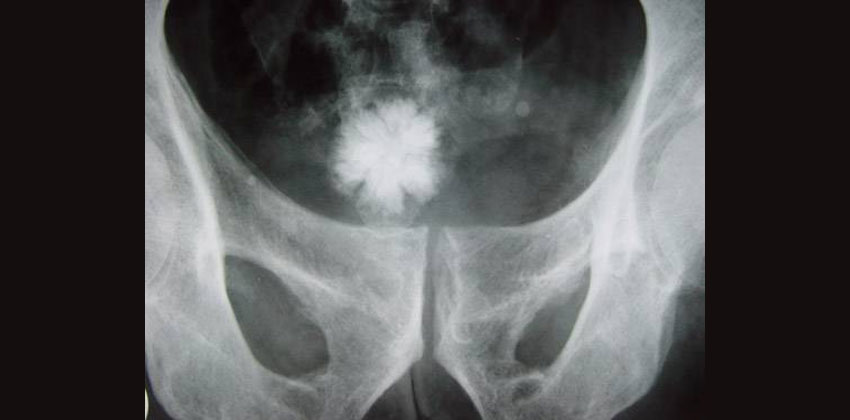

Λιθίαση ουροποιητικού είναι η δημιουργία λίθου ή λίθων μέσα στην αποχετευτική μοίρα του ουροποιητικού συστήματος (πυελοκαλυκικό σύστημα του νεφρού, ουτητήρας, ουροδόχος κύστη, ουρήθρα). Είναι η τρίτη κατά σειρά συχνότητας πάθηση του ουροποιητικού στον άνθρωπο, μετά τις ουρολοιμώξεις και τις παθήσεις του προστάτη.